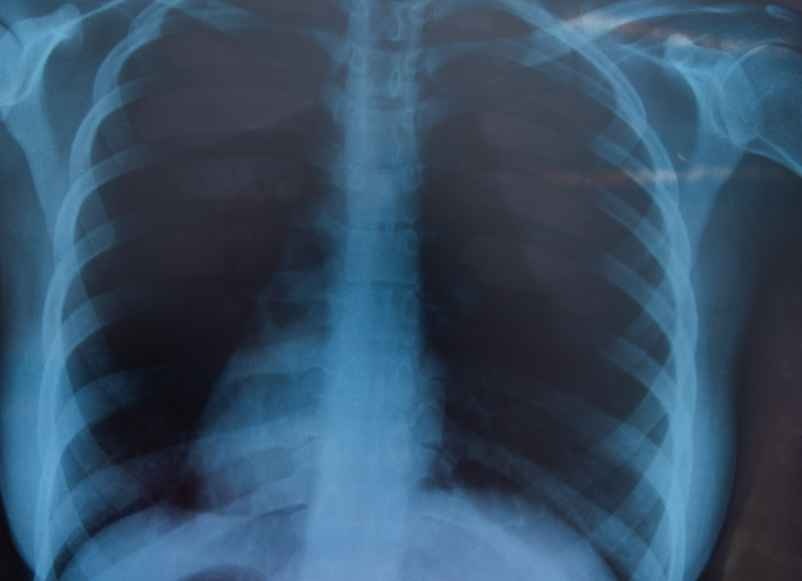

Le médecin peut prescrire une radiographie ou un scanner afin de différencier une côte fêlée d’une fracture plus grave et d’écarter toute lésion interne associée à la blessure. Un diagnostic précis permet de guider le traitement et de sécuriser la guérison. Apporter ses patients médicaux facilitent l’évaluation et le suivi.